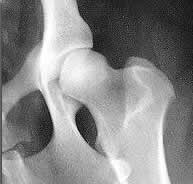

a) Displasia de la cadera.